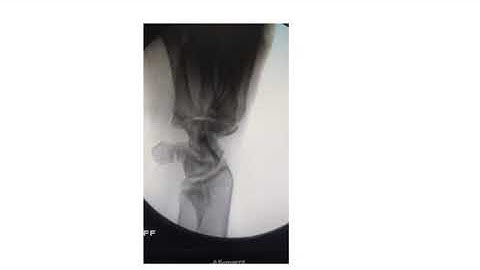

How to Avoid Complications during Percutaneous Fixation of Acute Scaphoid Fracture ? - Dr Anil Bhat